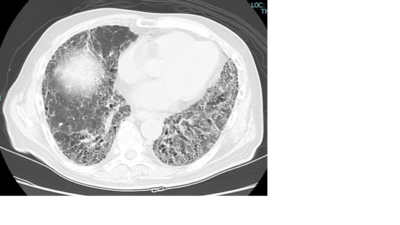

ざっくりいうと慢性的な炎症に伴い肺が固くなる(線維化)病気です。

肺は風船のように伸び縮みをし、スポンジのように柔らかいのですが、これが固くなり伸び縮みしなくなるイメージです。酸素の取り込みが低下し、肺が固くなるため通常よりも呼吸をするのに大きな力を要します。そのため消耗してしまい体重減少をきたす方もいらっしゃいます。

進行すると在宅酸素療法と言って家でも酸素吸入をしたり、外出時に酸素ボンベを持ち歩く必要があります。治癒は困難で一部を除き基本的にはずっと付き合っていき進行を遅らせることが主な目的になります。また肺癌の合併も多いとされており定期的な画像検査が必要です。

間質性肺炎を引き起こす原因としては

・特発性(原因がはっきりしない)

・リウマチ・膠原病(過剰な自己免疫が肺を攻撃して炎症を起こしてしまう)

・薬剤性

などがあります。採血検査・CT・肺機能検査などで間質性肺炎を引き起こす原因がないかを探っていきます。

特に最近では慢性過敏性肺炎といってカビやほこりなどの微細な粉塵の吸入が原因となり、肺に慢性的なアレルギー性炎症を起こす病気が注目されています。抗原によるアレルギー性慢性炎症が間質性肺炎を引き起こすため、適切な検査や抗原回避が重要とされています。住宅や職業に関わる抗原が多いとされており住宅関連ではカビや加湿器、古い木造家屋、エアコンを、トリ関連では鳥のフン、羽毛ふとん、ダウンジャケットなどが原因の可能性がありお話を聞きながら適宜検査を行っています。

治療としては抗炎症薬・抗線維化薬を用いることがありますが診断とその経過が重要です。必要に応じて大学病院等へご紹介も行っています。